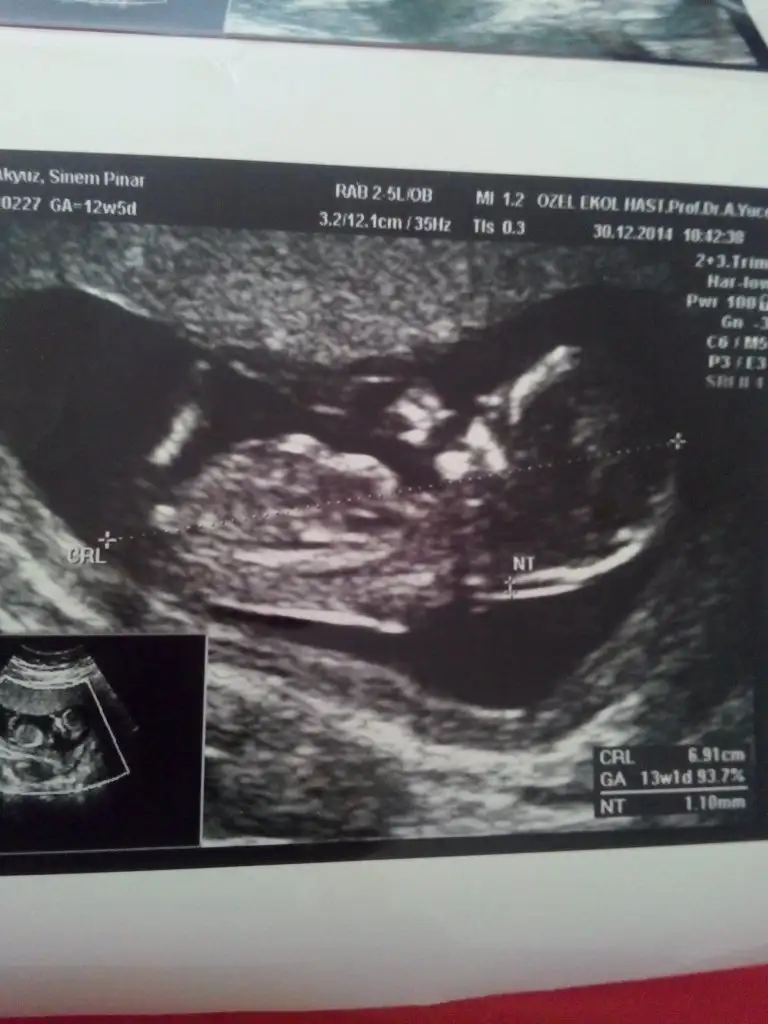

dr soylemeden siz gorun genital nub teorisi ( bebegin cinsiyeti)

kızlar sizce benmki kızmı erkekmi tam erkek gbi değil derecesi ama kız gbide değil sanki ya :D çözemedm var bsy orda ama IMG_20141230_131619.webp